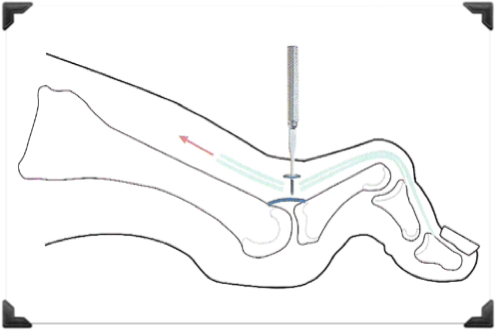

Principios de la Técnica

Corrección en el ápice o ángulo de la deformidad

Fijación Dinámica Blanda

- Fracturas Múltiples

- Osteotomías

- Liberación de Partes Blandas (Contractura)

- Tenotomías y Capsulotomías

- Realineación Anatómica

- Osteotomía Cuña Dorsal 1er Dedo

- Tenotomia del Flexor del 1er Dedo

- Osteotomía de Falange 2do Dedo